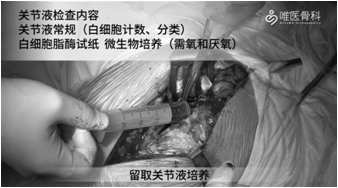

手术显露:沿原切口逐层切开,然后紧贴粗隆分离软组织,并松解臀大肌粗隆止点。切开关节囊,留取关节液培养,关节液检查内容包括关节液常规(白细胞计数、分类)、白细胞酯酶试纸检测,微生物培养(需氧和厌氧)。